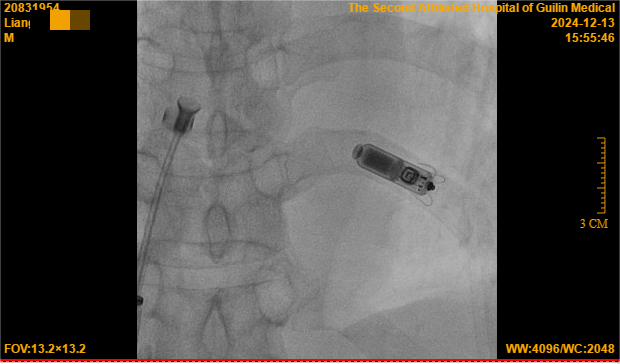

12月13日,心血管内科二病区团队通过局部麻醉方式为梁大爷进行了无导线起搏器的植入手术,用时仅45分钟,手术体验良好,几乎无痛感,让怕痛的梁大爷啧啧称赞,起搏器头端的“抓捕器”(电极)精准定位,一次性抓捕到合适的心肌,测试各项起搏参数均非常理想,术后仅有一个小穿刺口,局部加压止血即可。